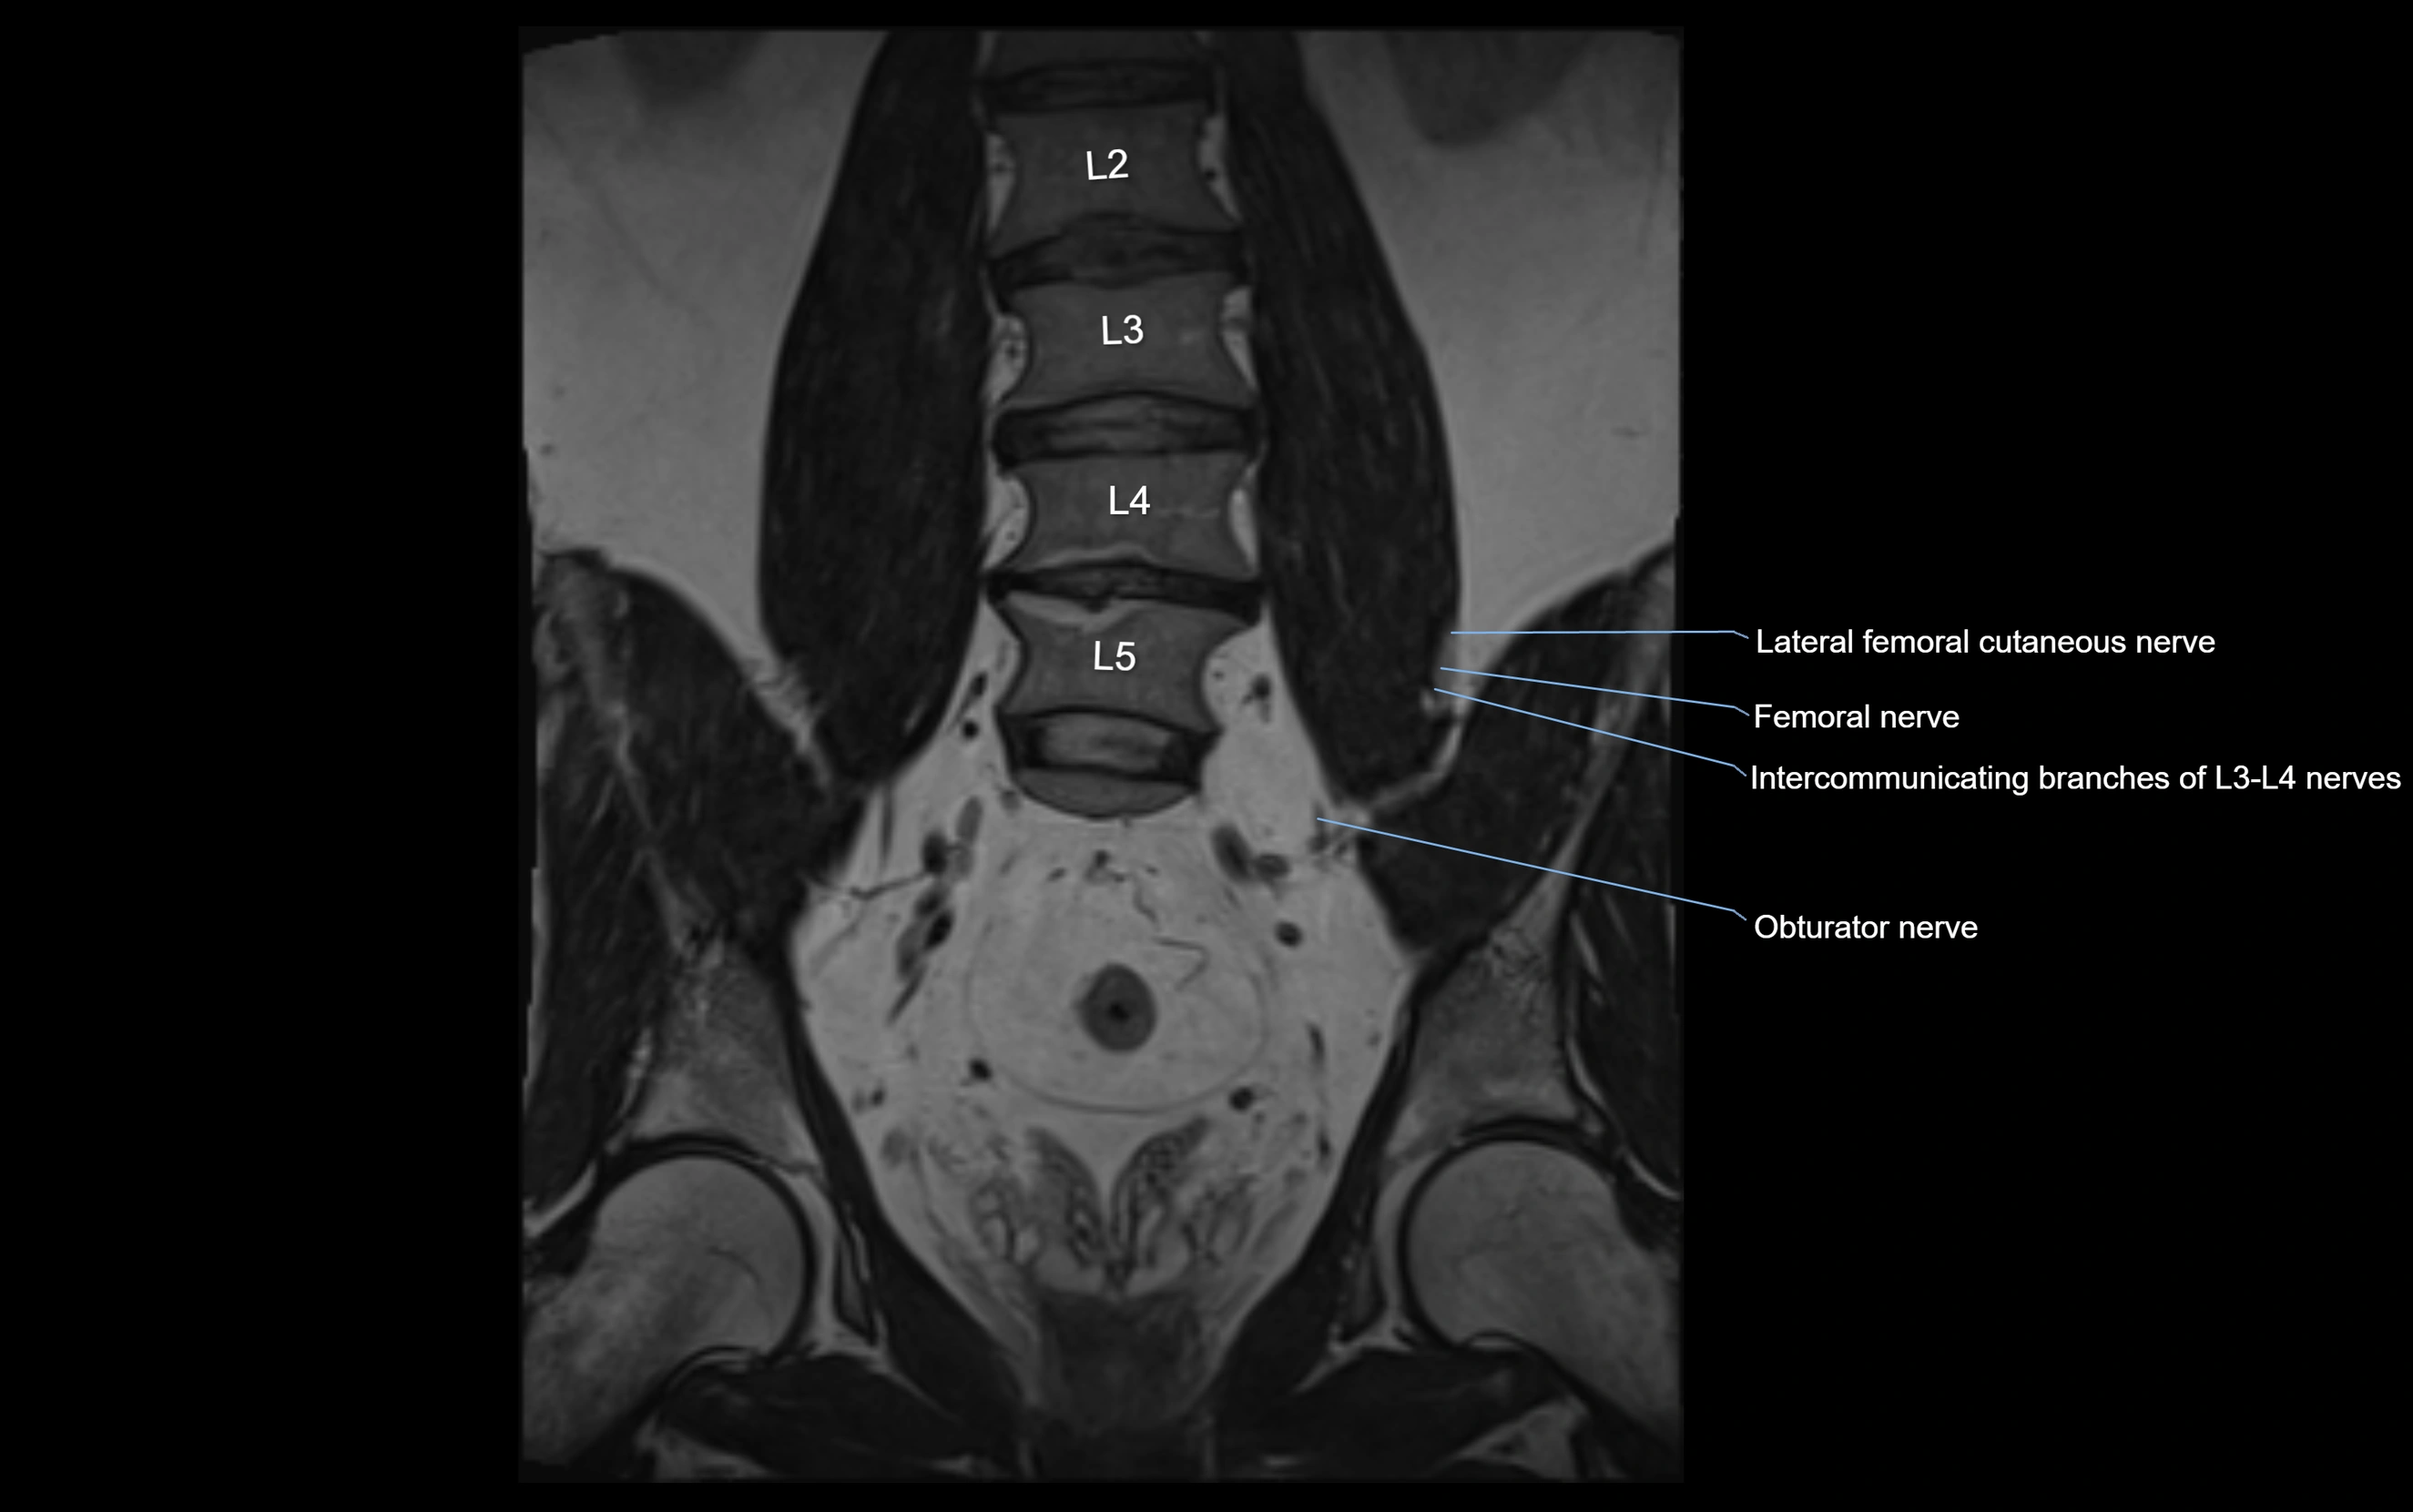

MRI image

image